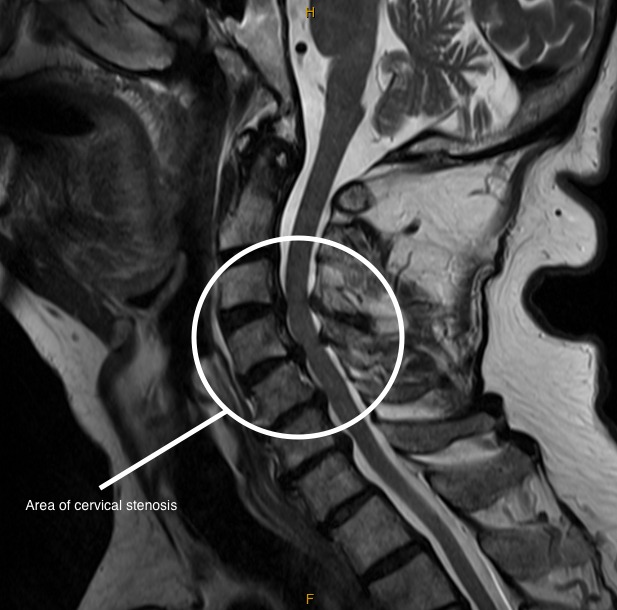

MRI